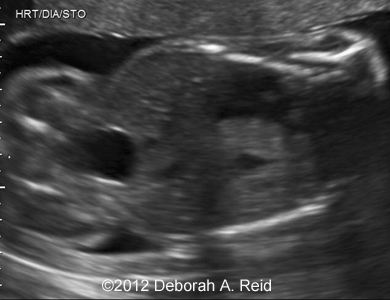

Ultrasound showed left-sided congenital diaphragmatic hernia with mild polyhydramnios.

The left-sided congenital diaphragmatic hernia contained a large portion of the bowel, spleen, stomach and the tip of the left lobe of the liver. In addition to the congenital diaphragmatic hernia, a sub-diaphragmatic sequestration was also noted which was confirmed by MRI.

Figure 1-10: The left-sided congenital diaphragmatic hernia contained a large portion of the bowel, spleen, stomach and the tip of the left lobe of the liver